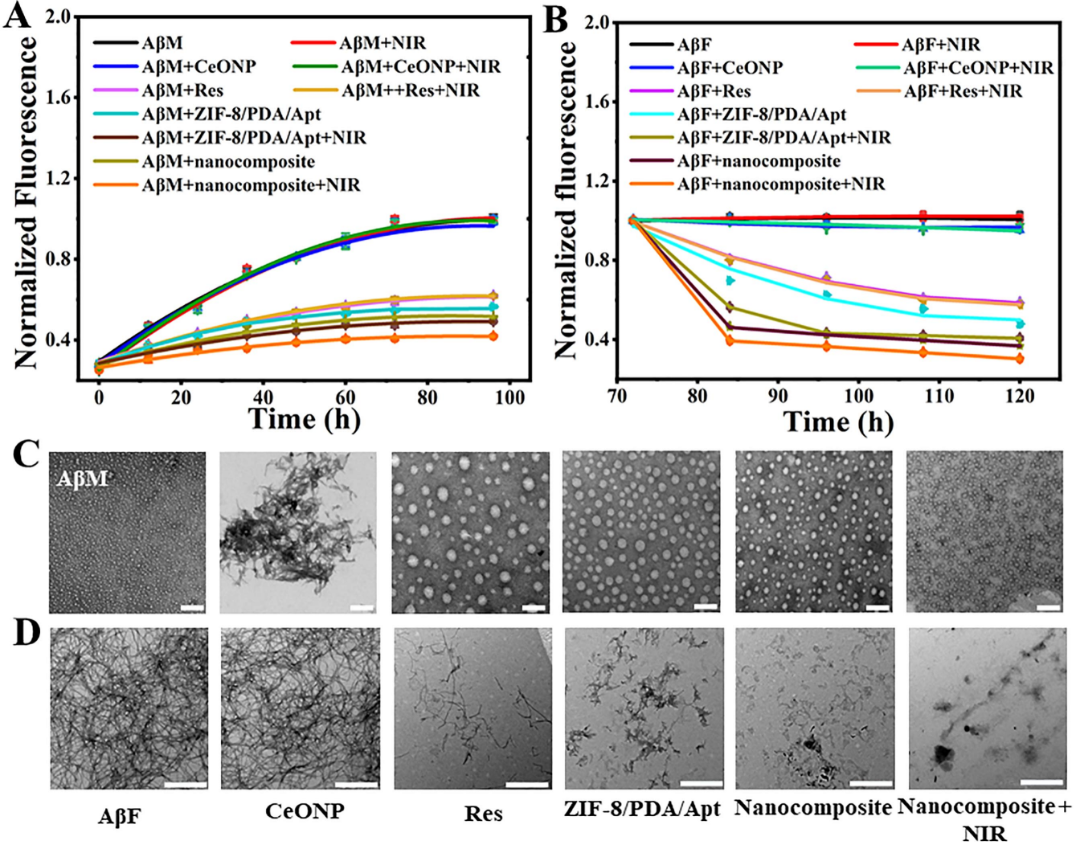

ТѕЉС╗гжњѕт»╣A╬▓УЄфуЙцжЏєуџётЙЂУ▒А��№╝їУђЃт»ЪС║єУ»ЦТјбжњѕтюеТіЉтѕХA╬▓уЙцжЏєС╗ЦтЈіУДБуд╗тјЪу║цу╗┤Тќ╣жЮбуџёуќЌТЋѕ�сђѓThTтњїTEMТЋѕТъюТЅ╣Т│е№╝ѕтЏЙтЏЏ№╝Ѕ��№╝їТјбжњѕТЌбУЃйтцЪТіЉтѕХA╬▓тЇЋСйЊуЙцжЏє��№╝їтЈѕУЃйУДБУЂџA╬▓тјЪу║цу╗┤��№╝їт╣ХСИћтюетЁЅуЃГуЁДт░ёСИІ��№╝їУ»ЦТђДУЃйУЃйтцЪУјитЙЌтбът╝║�сђѓу╗єУЃътєЁТ▓╗уќЌТЋѕТъюТЅ╣Т│е��№╝їУ»ЦТјбжњѕУЃйтцЪтюеу╗єУЃъТ░┤т╣│��№╝їТюЅућеТіЉтѕХA╬▓тЇЋСйЊуЙцжЏє��№╝їТЅФжЎцA╬▓OУ»▒т»╝уџёу╗єУЃътєЁУ┐ЄжЄЈROS��№╝їт╣ХСИћТјбжњѕуџётЁЅуЃГТђДУЃй��№╝їУЃйтцЪтбът╝║тЁХТ▓╗уќЌТЋѕТъю№╝ѕтЏЙС║ћ№╝Ѕ�сђѓтѕФуџё��№╝їJC-1сђЂTUNELС╗ЦтЈіCalcium-AM/PIТЪЊУЅ▓ТЋѕТъютЮЄТЅ╣Т│е��№╝їУ»ЦТјбжњѕтЈ»С╗ЦТюЅућетю░��№╝ЏсЂЕуфгУх┤т║ЦУ┤Ј╬▓У»▒т»╝уѕєтЈЉуџётЄІС║А�сђѓ

сђљтЏЙтЏЏсђЉТјбжњѕТіЉтѕХA╬▓уЙцжЏєС╗ЦтЈіУДБУЂџA╬▓тјЪу║цу╗┤уџёУђЃт»Ъ